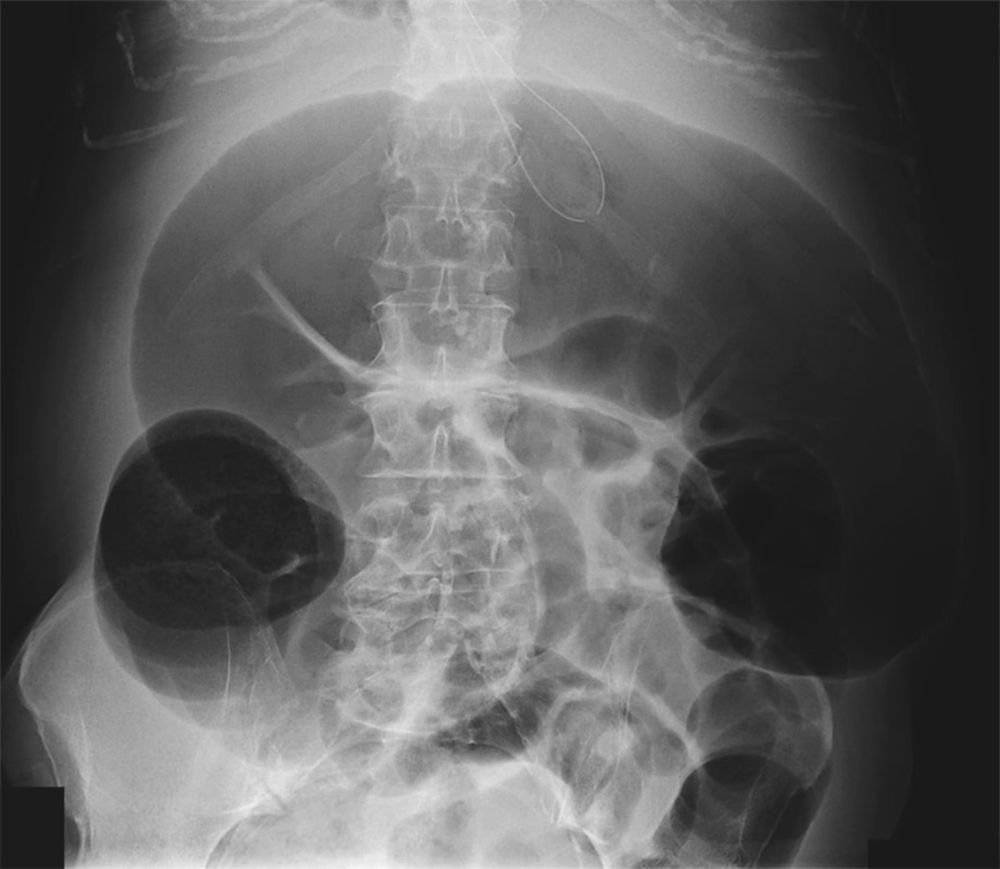

Abdominal Pain with Marked Abdominal Distention Post category:Spot Diagnosis Post published:July 15, 2022 Share on Facebook Share on X (Twitter) Share on Pinterest Share on Email Share on Reddit Abdominal Pain with Marked Abdominal Distention What is the diagnosis in this 70-year-old woman with abdominal pain and marked abdominal distention ? CLICK FOR FULL CASE AND ANSWER Share on Facebook Share on X (Twitter) Share on Pinterest Share on Email Share on Reddit Read more articles Previous PostRecurrent Pain and Bruising of Finger Next PostWell-demarcated Tan-colored Patch Covered with Coarse Dark Hairs You Might Also Like Patient with 1-week History of Lower Abdominal Pain and Dysuria December 22, 2021 Necrotic Skin Lesions on Nose, Ears, and Legs after Exposure to Cold January 15, 2022 A 74-year-old Woman With Lower Abdominal Pain, Nausea and Vomiting August 26, 2022